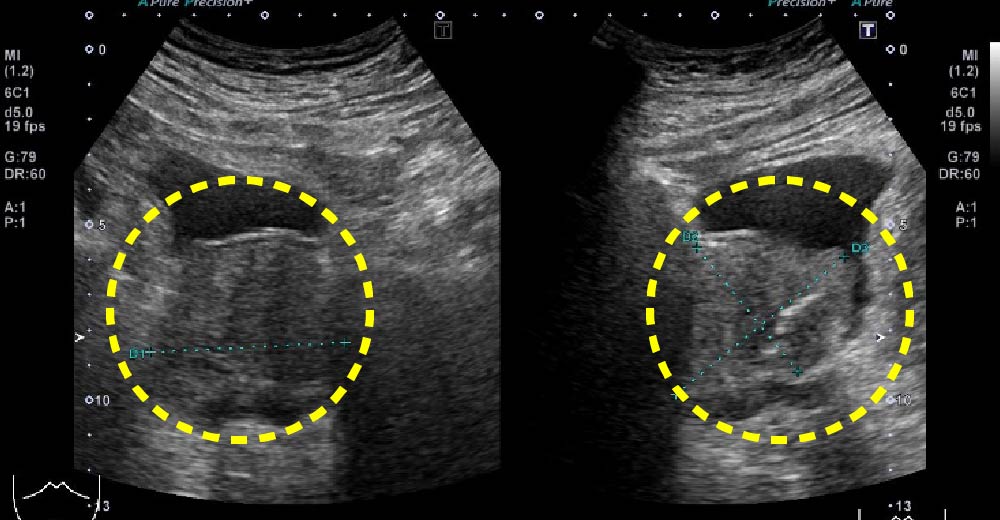

腎細胞がん症例です。

エコーで、内部不均一な腫瘤が確認されます。

腎細胞がん 腎細胞がん